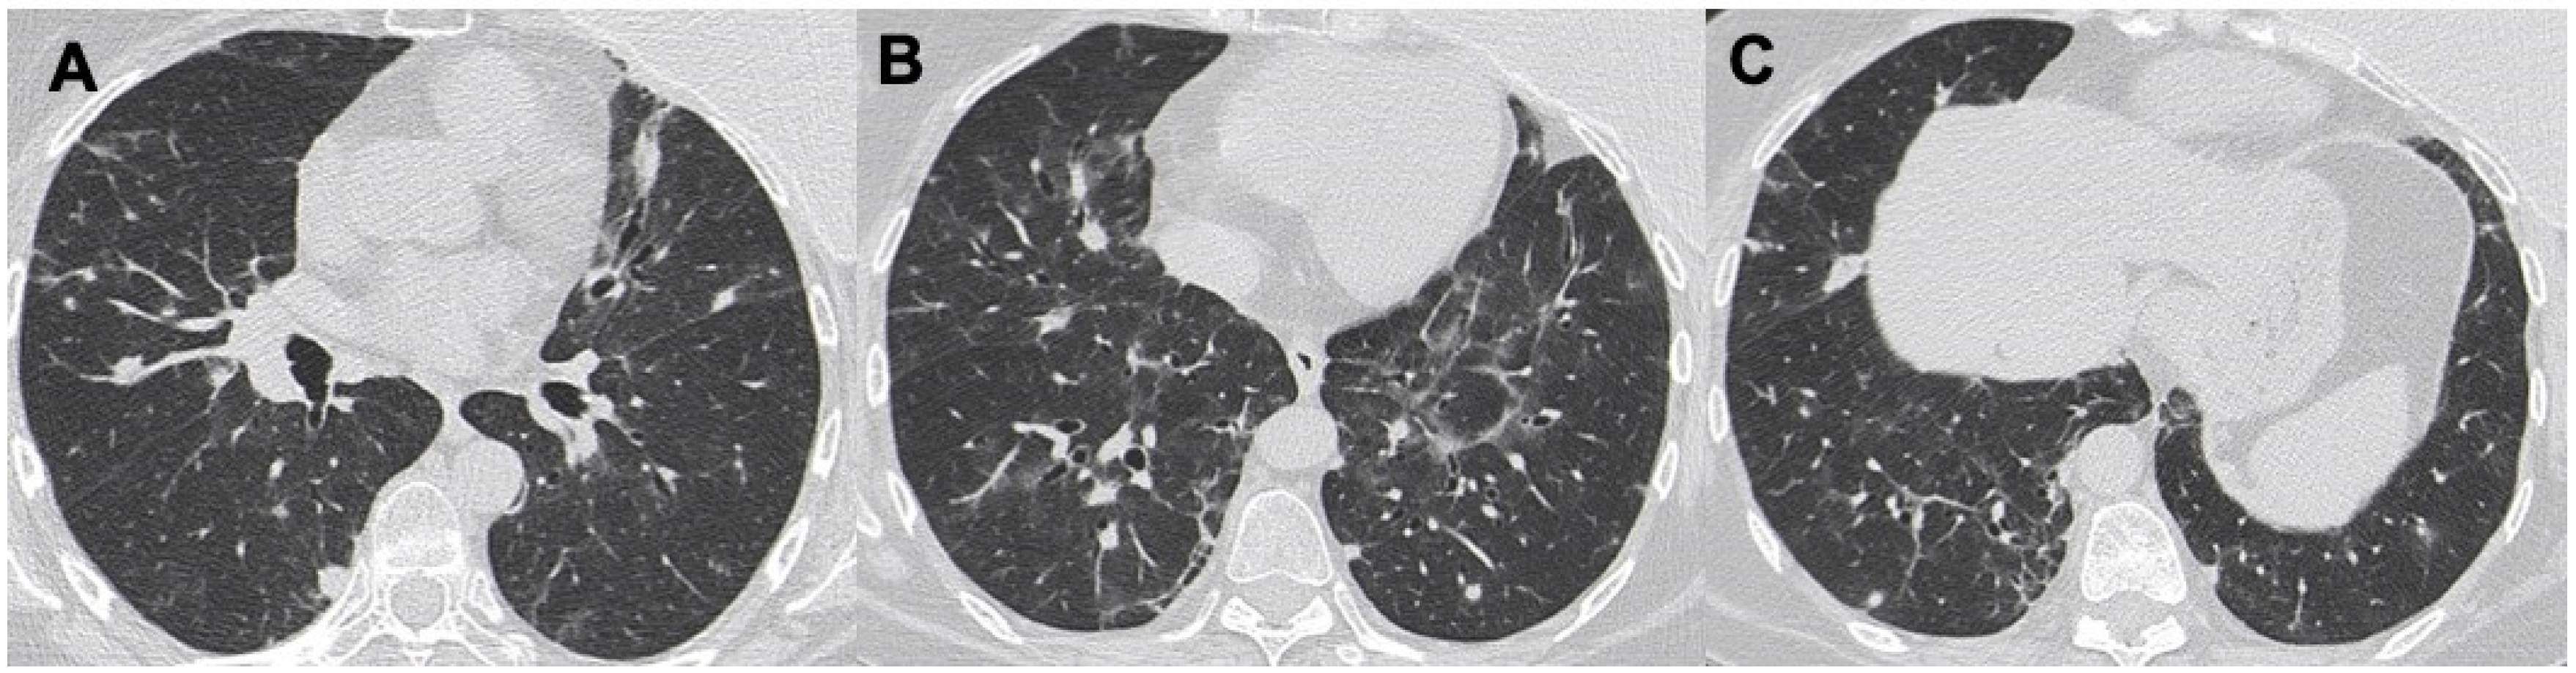

3.1. Consolidations

3.3. Ground-Glass Opacities

| MALT | Consolidations, bronchovascular distribution without topographic predominance, lobar-like pneumonia (rare), ±bulging fissure sign, ±angiogram sign, ±air bronchogram; less frequently nodules, masses and GGO; interstitial involvement (very rare) | Neoplasms, lobar or focal atelectasis, infections (Klebsiella pneumoniae), OP, LIP, NLH, sarcoidosis |